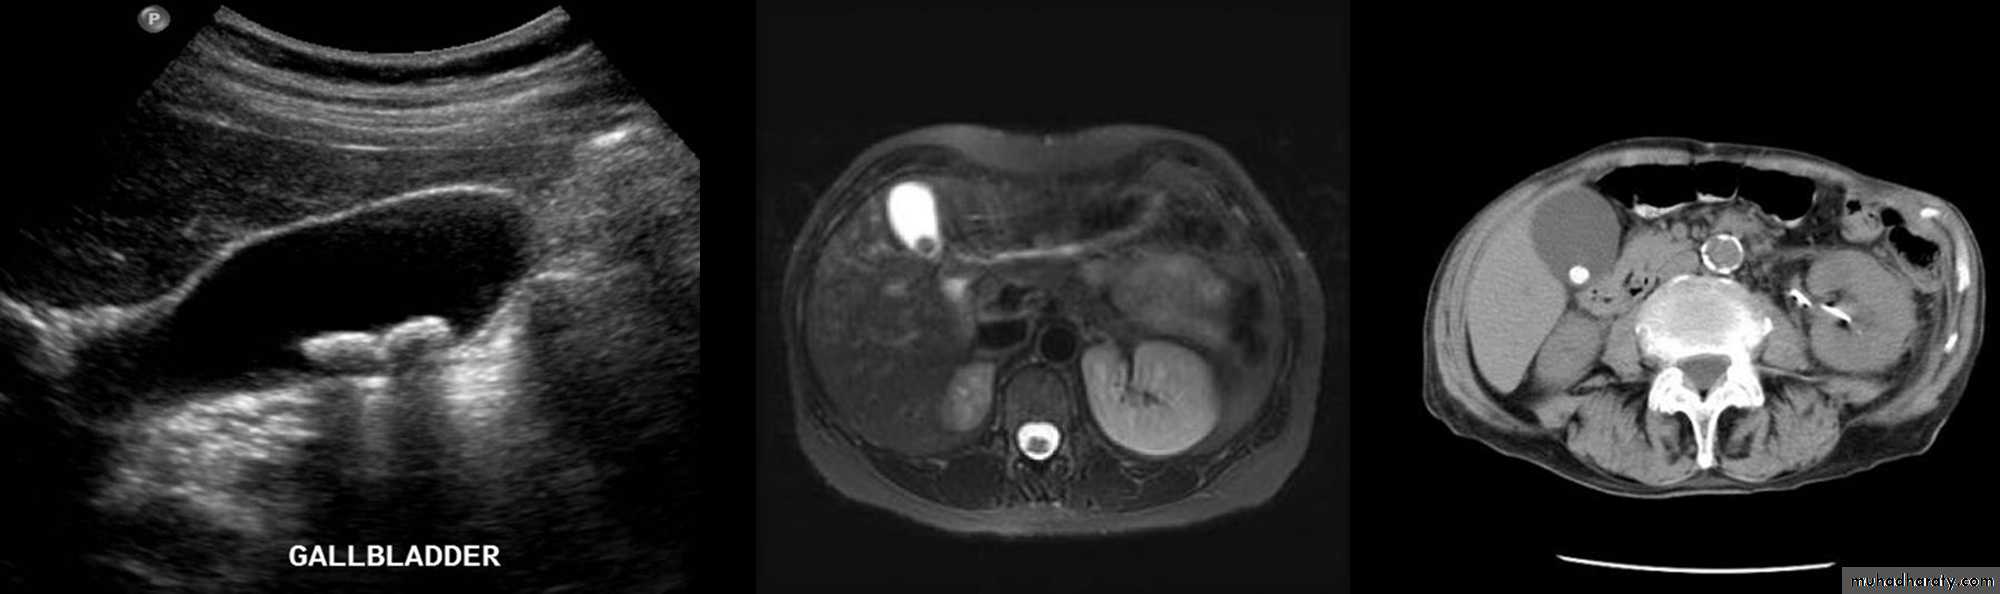

Gall Stones

• On US, stones are strongly echogenic with acoustic shadow (which is not seen with polyps).

• US is not reliable for detecting stones in CBD which are better demonstrated by MRCP.

Cholecystitis

• US features of early or uncomplicated acute cholecystitis:

• Gall stones (which may be impacted in the GB neck or cystic duct)

• Gall bladder wall thickening

• Gall bladder distension

• Positive sonographic Murphy's sign (focal tenderness over the GB when compressed by the US transducer)

• US features of chronic cholecystitis are thick wall and GB contraction.

• CT is much less sensitive than US for the detection of gallstones.

• CT signs of gallbladder inflammation include thickening of the gallbladder wall with infiltrative streaking in adjacent fat.